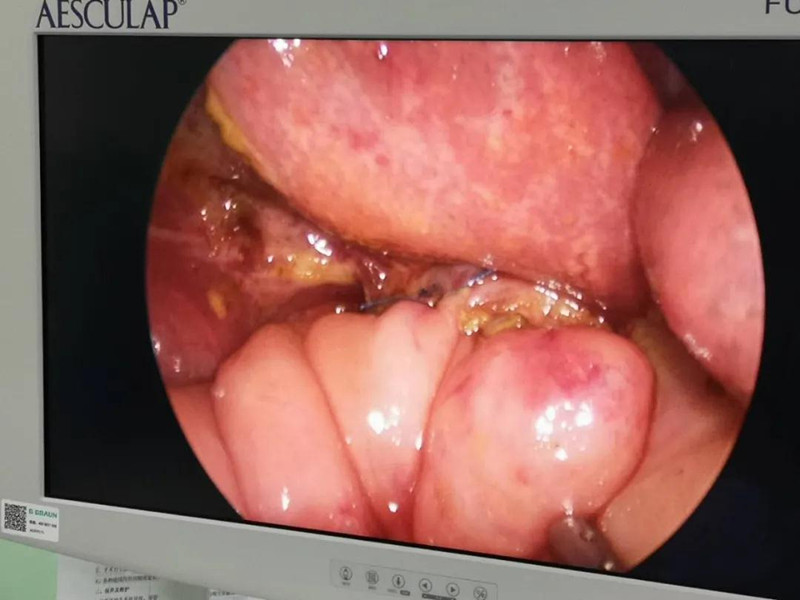

最近半个月,长春市26个月女宝馨馨(化名)脸色不好,全身发黄严重,还伴随发烧。9月23日,馨馨被家人带到啪啪网 诊治。经检查,馨馨全身发黄是因为患有黄疸,而黄疸的出现是因为胆总管发生病变,“胆总管呈现囊性扩张,下边出口被堵住,胆汁进不到肠腔里,导致孩子出现黄疸、肝功不好、白土便症状。而且胆总管胀大后,还有癌变的风险,”普外、新生儿外科主任崔钊说,馨馨需要尽快手术。为了减少损伤,崔钊主任团队制定的方案是单孔腹腔镜下胆总管囊肿根治手术。

术前准备完毕。 9月25日,馨馨进入手术室。由崔钊主任带队,按照术前设计的方案,经过8个小时的奋战,手术成功了。馨馨肝总管以下病变的胆总管及胆囊全部切除,肝总管断面与肠管吻合接上,让胆汁直接流到肠腔里,帮助消化。如术后不出现胆瘘、肠瘘,没有梗阻,馨馨以后就可以正常生活了。目前馨馨恢复得很好,黄疸渐渐缓解,肝功正常,白细胞也降下来了,排气、排便都没问题,引尿管里也没有异常东西。